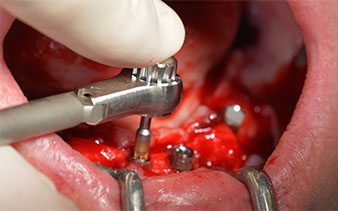

Les piliers angulés (35°) ont été vissés pour compenser la divergence des implants distaux. Ainsi, le profil

d'émergence de tous les implants doit être le plus perpendiculaire possible par rapport au plan occlusal. Il s'agit

d'une condition préalable à la pose en occlusion de la prothèse provisoire puis permanente (Fig. 15 et 16).